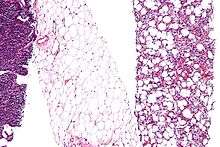

A cell that can differentiate into all cell types of the adult organism is known as pluripotent. Such cells are called embryonic stem cells in animals and meristematic cells in higher plants. A cell that can differentiate into all cell types, including the placental tissue, is known as totipotent. In mammals, only the zygote and subsequent blastomeres are totipotent, while in plants many differentiated cells can become totipotent with simple laboratory techniques. In cytopathology, the level of cellular differentiation is used as a measure of cancer progression. "Grade" is a marker of how differentiated a cell in a tumor is.[4]

Three basic categories of cells make up the mammalian body: germ cells, somatic cells, and stem cells. Each of the approximately 100 trillion (1014) cells in an adult human has its own copy or copies of the genome except certain cell types, such as red blood cells, that lack nuclei in their fully differentiated state. Most cells are diploid; they have two copies of each chromosome. Such cells, called somatic cells, make up most of the human body, such as skin and muscle cells. Cells differentiate to specialize for different functions.[5]

- Hematopoietic stem cells (adult stem cells) from the bone marrow that give rise to red blood cells, white blood cells, and platelets

- Mesenchymal stem cells (adult stem cells) from the bone marrow that give rise to stromal cells, fat cells, and types of bone cells